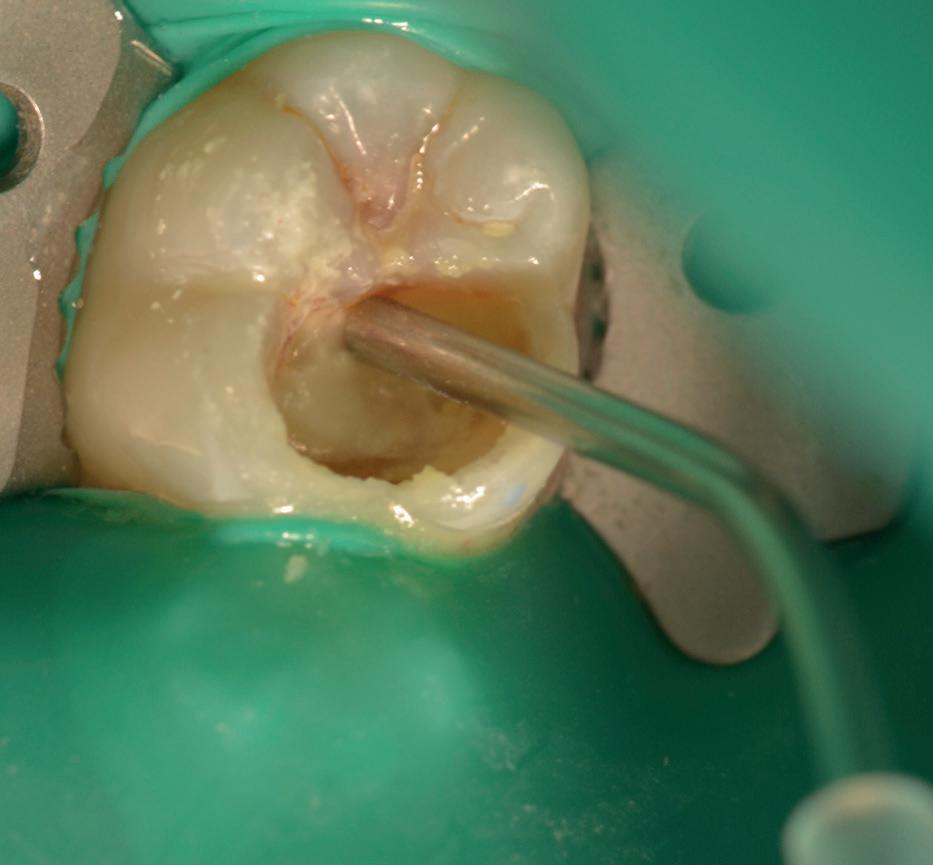

Predictable management of a deep carious lesion, page 27